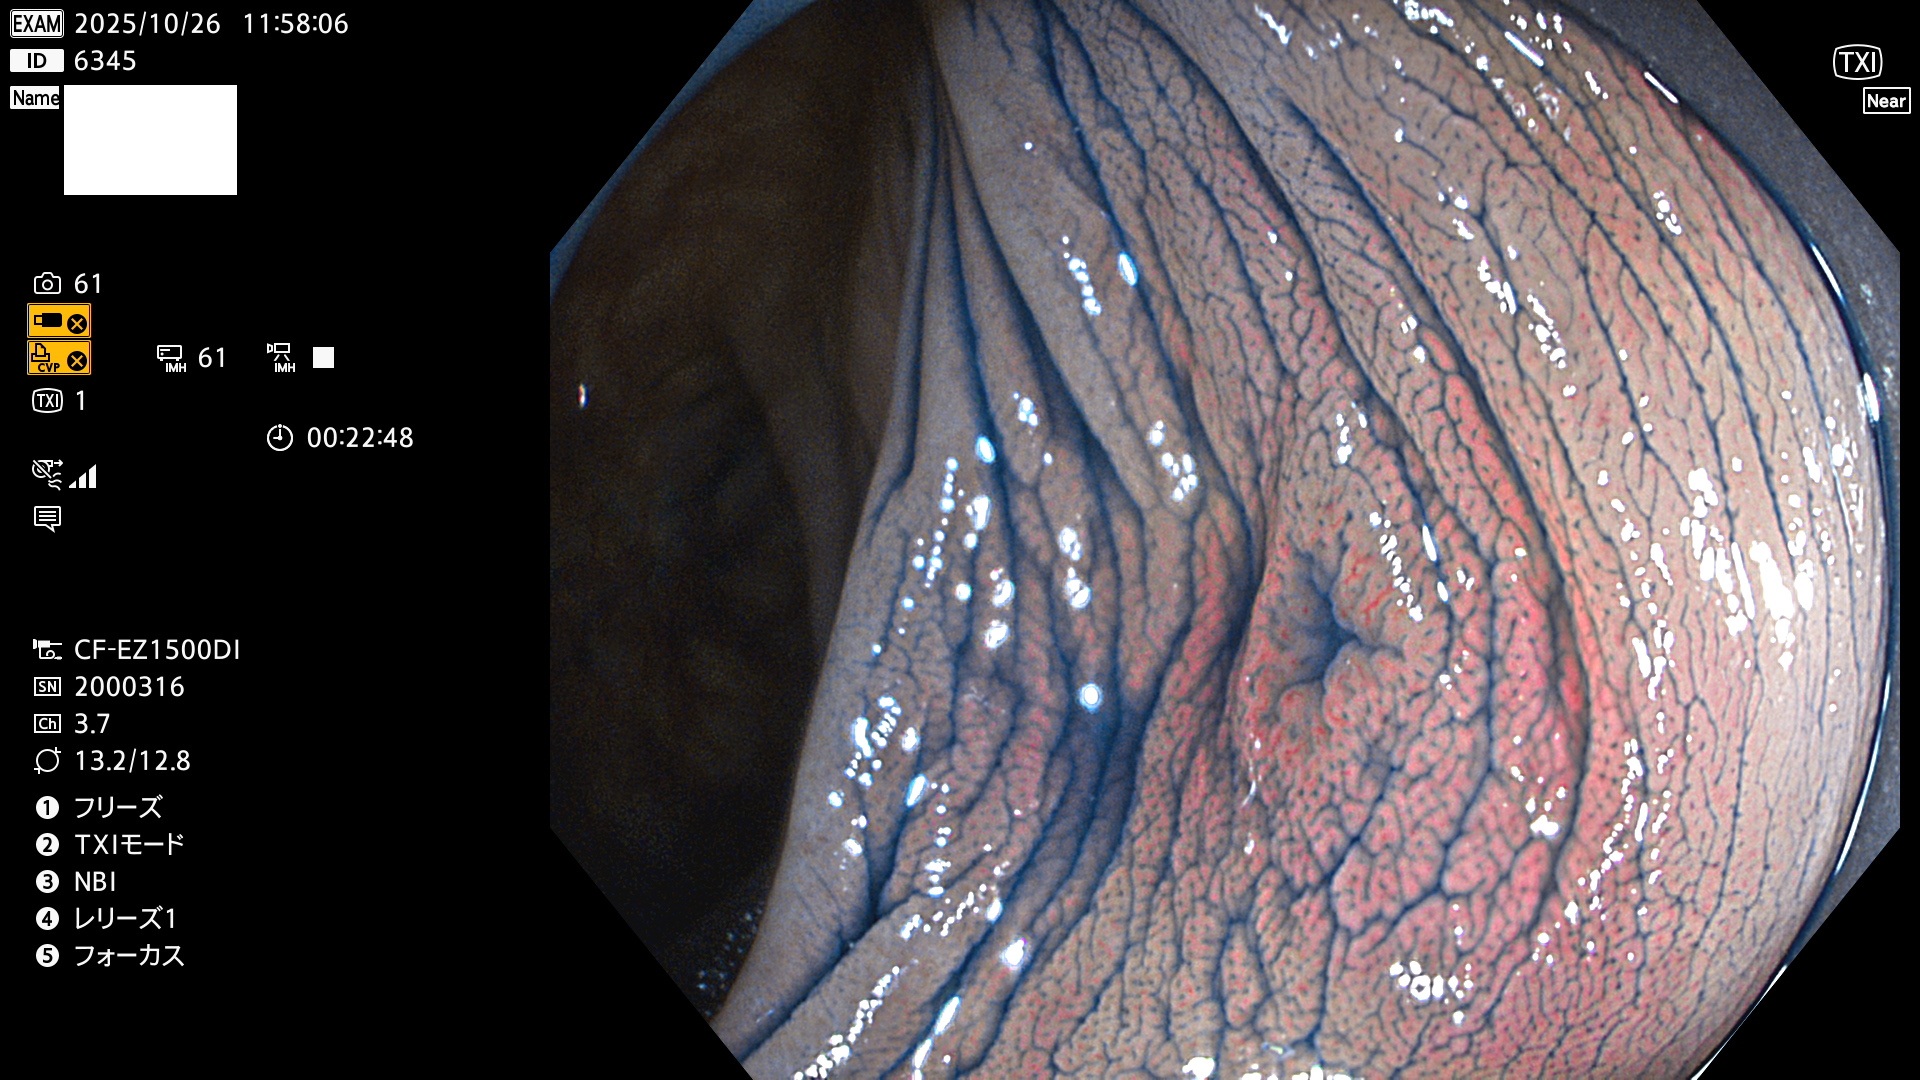

完全に平坦な物をUb、陥凹している物をUcと呼びます。Ubは認識が困難で、Ucはびらん(炎症)と紛らわしいために見落とされやすく、「内視鏡後・大腸癌」の原因になります。

毎週の検査(木・金・土・日)に発見されたUbとUc型・腺腫を、その週の日曜の夜にUPし1週間、提示します。

2025年10月23日〜10月26日の4日間(40件)6個 (Uc_ADR=6個/40人=15%)